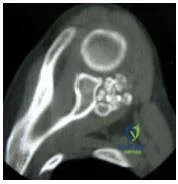

This slide is a computed tomogram of the shoulder of a 22-year-old rugby player. The most likely diagnosis is:

Orthopedic Prometric Exam Chapter 3 Image

Explanation

The computed tomogram shows a posterior avulsion of the glenoid rim and an impaction fracture of the anterior aspect of the humeral head consisted with a prior posterior dislocation.